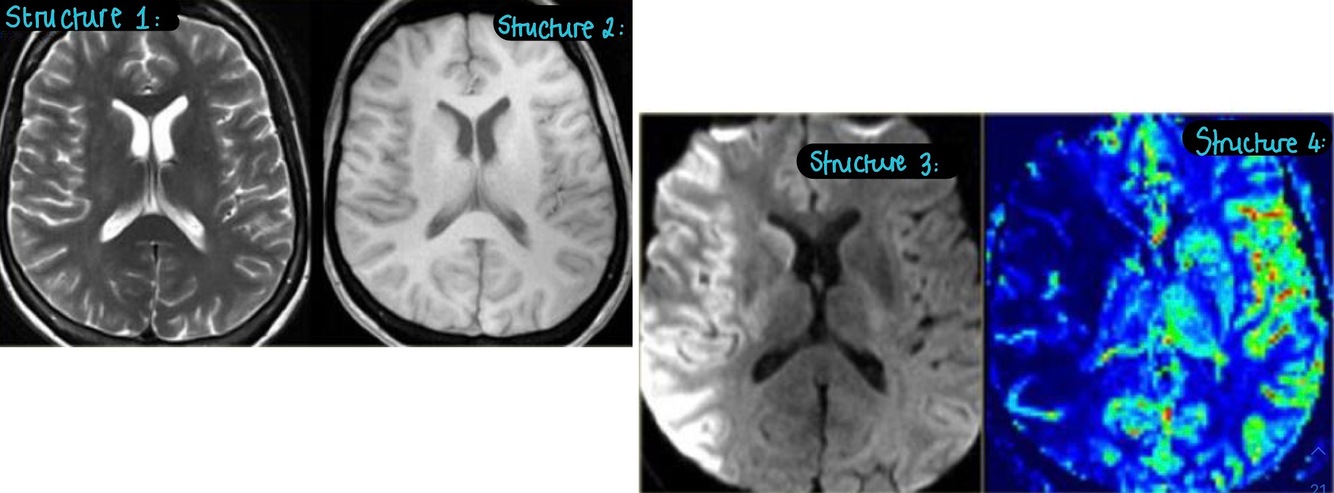

1. Label these images?

STRUCTURE 1:

- this is a T2 Weighted image

- it cannot detect the stroke

STRUCTURE 2:

- cannot detect the stroke

STRUCTURE 3:

- this is a Diffusion Weighted Image

- the areas of decreased diffusion are bright

- this is where the stroke is

STRUCTURE 4:

- this is a Perfusion Image

- the areas of decreased diffusion are dark

- this is where the stroke is taking place